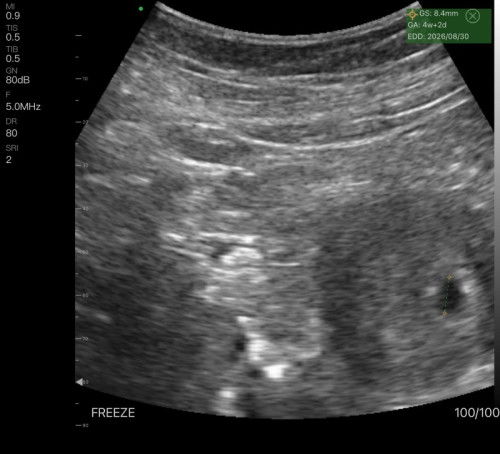

Gestational Sac Only

Normal pa ba to sa Age ni baby? Last mens ko po oct. 28, positive na ako sa PT nung December 4, then nagpacheck up ako December 9, thick endometrium palang po nakita tapos bumalik po ako ng December 23, ganto palang po nakita SAC palang na maliit, normal po ba to yung laki ng sac sa last mens ko? Salamat po